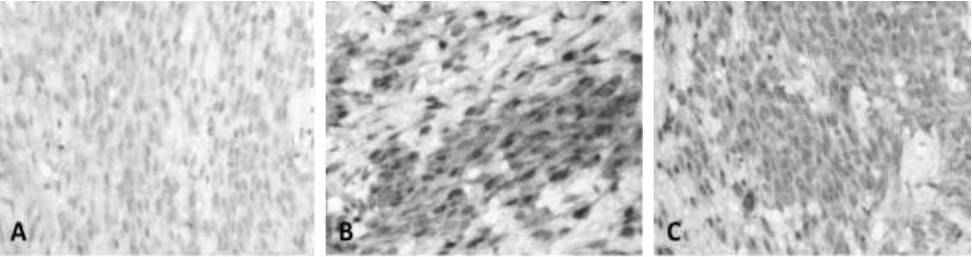

To determine the tissue origin of the cells, an indirect immunohistochemistry was performed using the streptavidin-biotin-peroxidase technique with polyclonal antibodies, which tested positive for la glial fibrillary acidic protein (Figure 2, A), S-100 protein (Figure 2, B), and vimentin (Figure 2, C).

A. Fibrillar Acid Protein Glial, in a discrete but uniform pattern in most neoplastic cells.

B. Protein S-100, very notorious marking in groups of tumor cells

C. Vimentin, uniform labeling in cell groups of the neurilemoma.

Figure 2 Neurilemmoma. Canine, Shar-pei, male, 4 years. Immunolabeling with HRP. 400X.